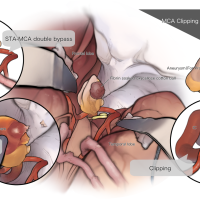

監修:谷川 緑野 / 札幌禎心会病院脳卒中センター

術後イラストシリーズ